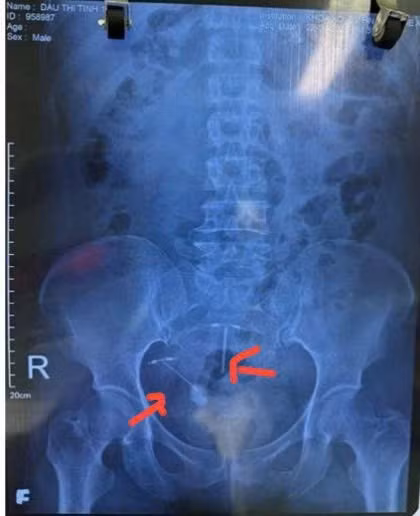

Hình ảnh phim X-quang trước mổ có 2 vòng tránh thai: Vòng bên trái dưới đâm vào bàng quang tạo sỏi, vòng bên phải trên đúng vị trí nằm trong buồng tử cung - Ảnh BVCC

Bệnh nhân được chuyển vào khoa Ngoại Tiết niệu, Bệnh viện Hữu nghị đa khoa Nghệ An làm đầy đủ các xét nghiệm như siêu âm, chụp X-quang, chụp cắt lớp vi tính ổ bụng… được chẩn đoán xác định vòng tránh thai lạc, xuyên thủng vào bàng quang và hình thành tạo sỏi trong bàng quang (kích thước viên sỏi 3×4 cm).